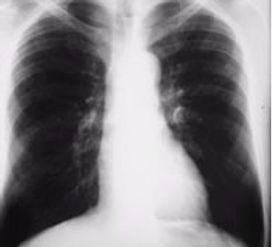

肺疾患の早期発見のために

呼吸機能検査